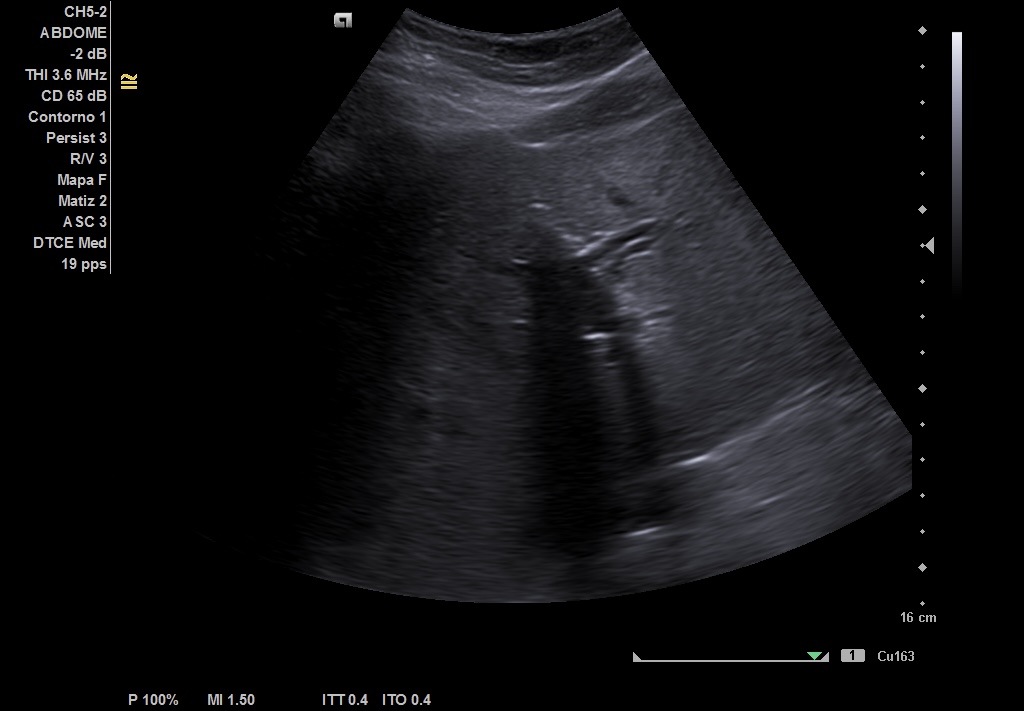

Hallazgos ecográficos

Realizamos ecografía abdominal en el Centro de Salud en el momento de la consulta y visualizamos: Colelitiasis y dilatación de la vía intra y extrashepática sin observar claramente causa obstructiva.

• Nueva ECO de abdomen y colangioRMN en las que se observa: colelitiasis. Vía intra y extrahepática dilatada, sugestivo de coledocolitiasis distal de 5 mm, que se extrae con CPRE.

Pudimos confirmar que se trataba de una ictericia por obstrucción de vía biliar secundaria a litiasis de vesícula, con mismas imágenes encontradas en ECO reglada y en RMN realizadas en centro Hospitalario que las halladas en el Centro de Salud.